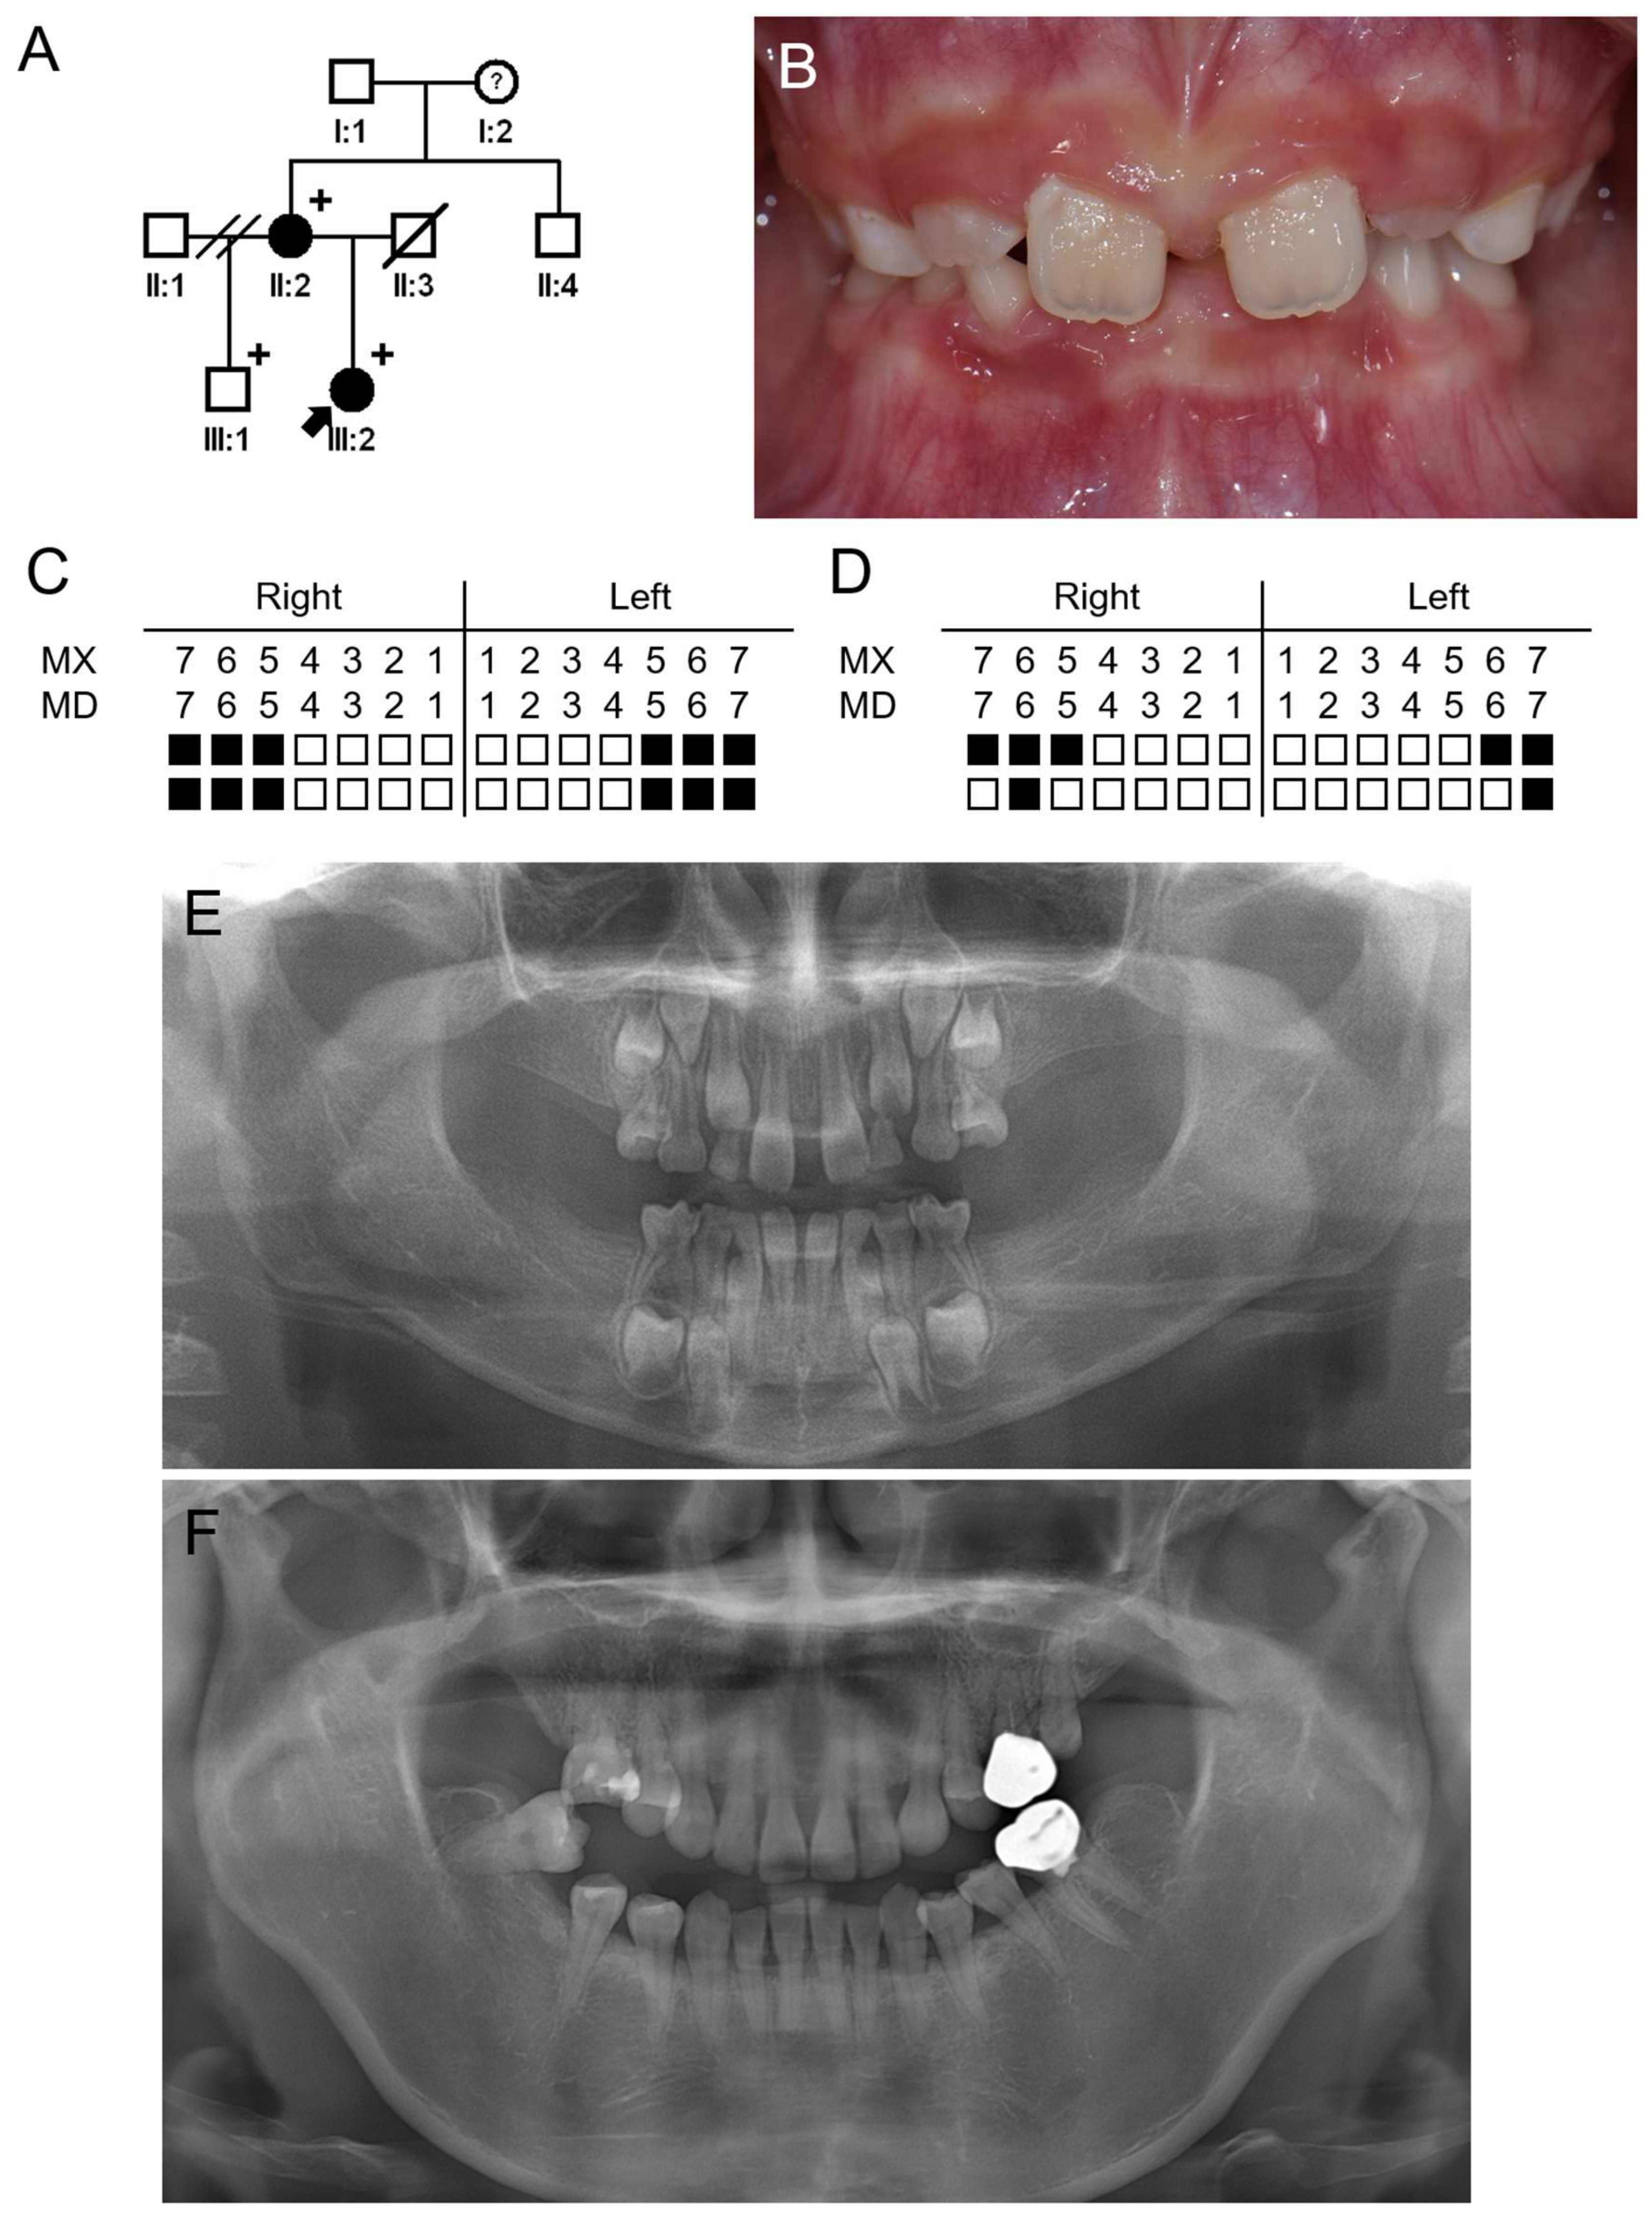

3.2. Family 2